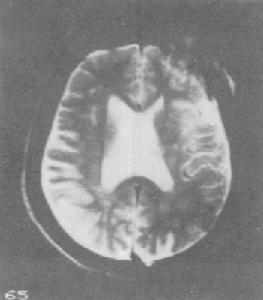

5、患者腦電圖可出現低波幅慢,波CT檢查顯示腦室擴大,腦皮質特別是額葉顯著萎縮等。

1、心電圖、腦電圖、腦CT或MRI檢查,有鑑別診斷及中毒程度評估意義。